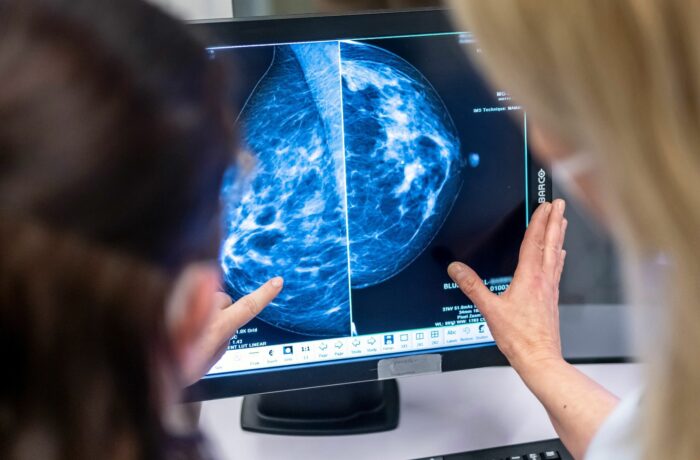

Laut IARC sind im Jahr 2022 9,7 Millionen Menschen an Krebs gestorben. Die gängigsten Krebsarten waren Lungen-, Brust- und Darmkrebs. Bei Frauen war Brustkrebs die am weitesten verbreitete Form, gefolgt von Lungen- und Darmkrebs. Bei Männern war Lungenkrebs die häufigste Form, gefolgt von Prostata- und Darmkrebs. Die IARC hat Daten aus 185 Ländern analysiert.

Im Jahr 2022 wurden 2,5 Millionen Menschen mit Lungenkrebs diagnostiziert. Dies entspricht 12,4 Prozent aller erfassten Krebsfälle. Bei 2,3 Millionen Frauen wurde Brustkrebs diagnostiziert, was 11,6 Prozent aller Krebsfälle ausmacht. 1,9 Millionen Menschen erhielten die Diagnose Darmkrebs (9,6 Prozent). Danach waren Prostata- und Magenkrebs am häufigsten.

Lungenkrebs war auch für die meisten Todesfälle durch Krebs verantwortlich: 1,8 Millionen. Nach Angaben der IARC entspricht dies 18,7 Prozent aller Menschen, die 2022 an Krebs gestorben sind. 900.000 Menschen starben an Darmkrebs (9,3 Prozent) und 670.000 an Brustkrebs (6,9 Prozent). Die Anzahl der Menschen, die fünf Jahre nach einer Krebsdiagnose noch am Leben waren, lag im Jahr 2022 laut IARC bei 53,5 Millionen. Im Jahr 2020 lag diese Zahl laut einer früheren Mitteilung der IARC bei 50,6 Millionen – aber auch hier gilt: Direkte Vergleiche sind aufgrund der ständigen Verbesserung der Erhebungsmethoden schwierig, so die Agentur.